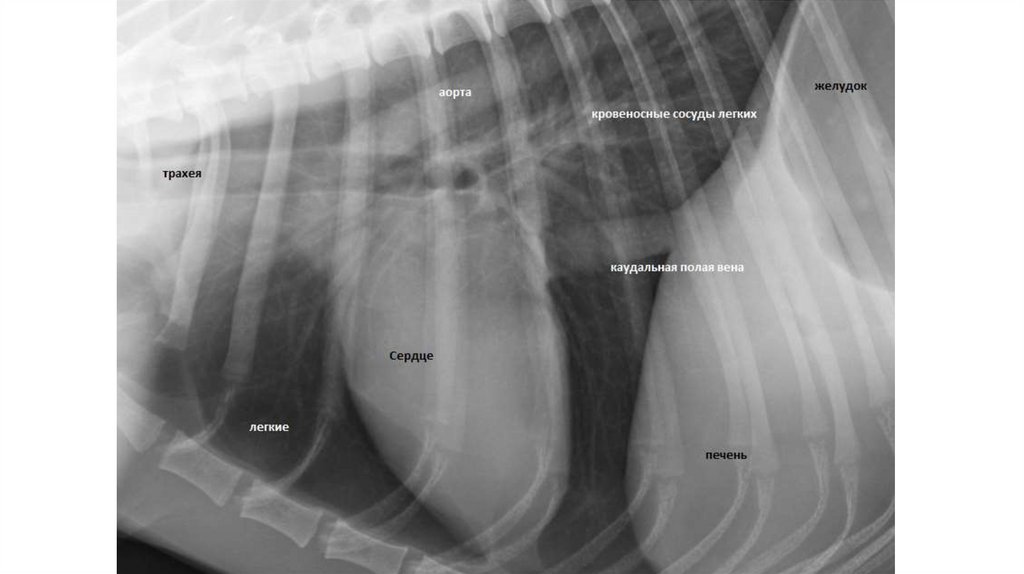

Исследование ССС

• Исследование сердечно-сосудистой системы животных проводят в

определенной последовательности: общий осмотр, осмотр и пальпация

сердечной области, перкуссия сердечной области, аускультация

сердца, исследование кровеносных сосудов (артерий и вен),

инструментально-функциональные исследования сердечнососудистой системы (электрокардиография, УЗИ, рентгеноскопия,

определение артериального и венозного кровяного давления и др.)